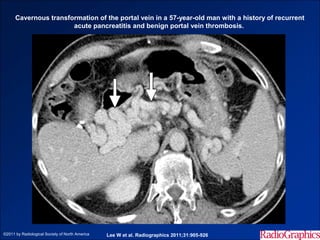

Cavernous transformation of the portal vein in a 57-year-old man with a history of recurrent

acute pancreatitis and benign portal vein thrombosis.

©2011 by Radiological Society of North America   Lee W et al. Radiographics 2011;31:905-926

• #29 Cavernous transformation of the portal vein in a 57-year-old man with a history of recurrent acute pancreatitis and benign portal vein thrombosis. Axial contrast-enhanced CT image obtained during the venous phase shows multiple serpentine enhancing collateral vessels (arrows) at the hepatic hilum and an obliterated main portal vein, findings indicative of cavernous transformation of the portal vein in the setting of long-standing thrombosis.